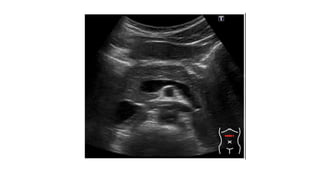

USG Abdomen Detect gallstones

Identify area of necrosis –hypoechoic regions

Transverse ultrasound demonstrates

diffuse enlargement of the pancreas ,

which appears abnormally hypoechoic